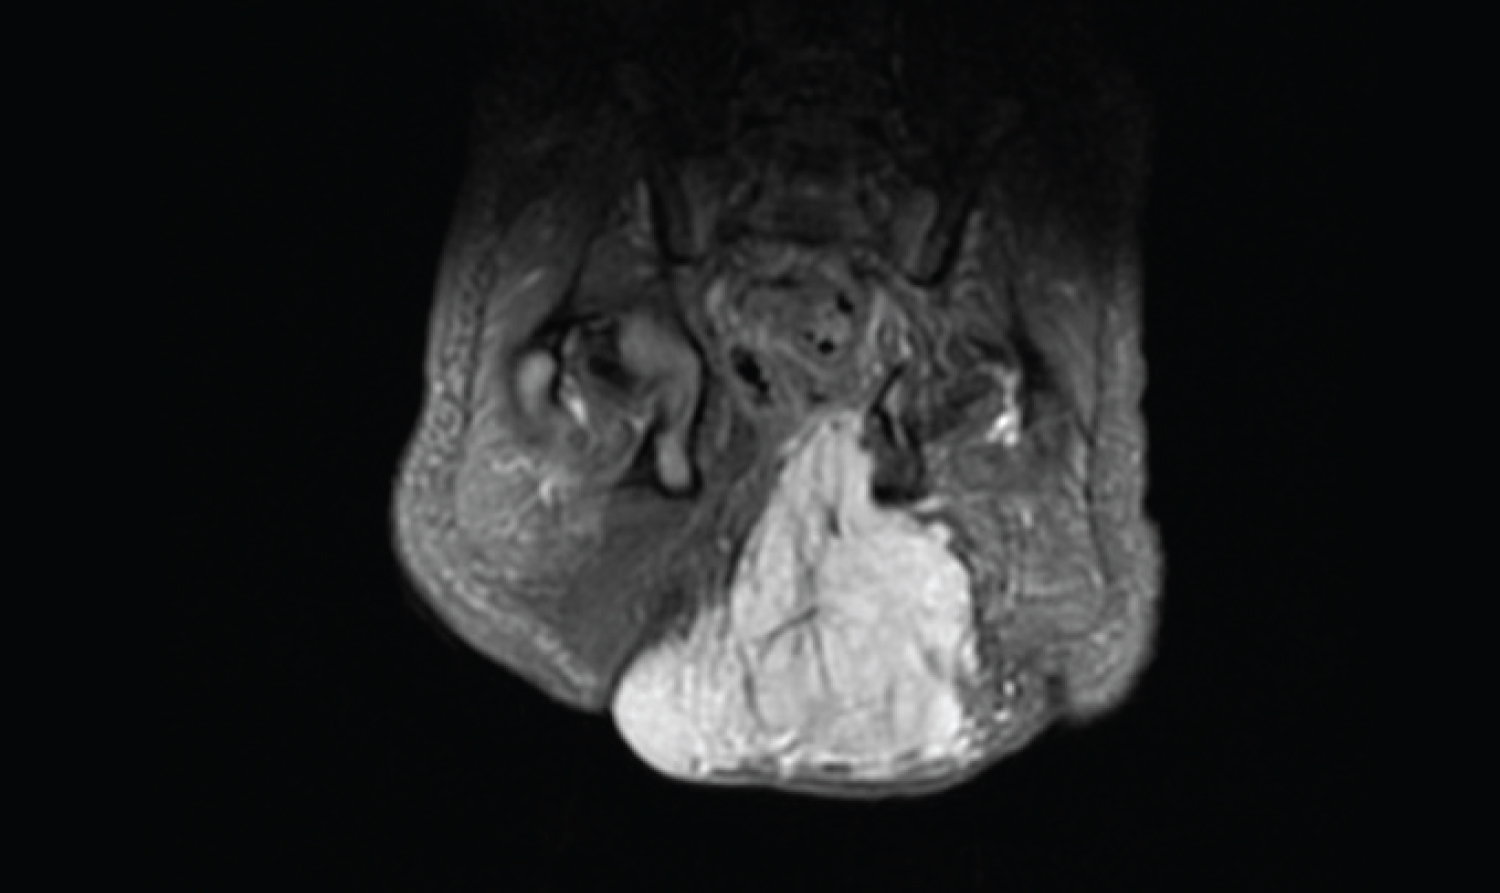

A male newborn with a gestational age of 39 weeks and 2 days, with appropriate weight for gestational age, was born by eutocic delivery. Pregnancy surveillance was unremarkable, with maternal serologies and obstetric ultrasounds considered normal. In the delivery room, an adherent red-violaceous rounded lesion in the left gluteal region, with hard consistency, peripheral pale halo and telangiectasias, measuring approximately 5 cm, was observed (Figure 1). The newborn was clinically well, the physical examination was otherwise normal and there were no other skin lesions. Complete blood count and coagulation factor tests were normal, excluding Kasabach-Merritt phenomenon. Ultrasound revealed a solid, heterogeneous, hyperechoic, bulky mass with imprecise limits and extent in depth, involving the muscular and subcutaneous compartments. Doppler study showed hypervascularity and a few large vessels with high flow. No other masses in the pelvic cavity or signs of anchored marrow were observed. Magnetic resonance angiography revealed a lesion with a pyramidal configuration with 5.3 cm of majoraxis, occupying the subcutaneous region and the internal side of the large and medial gluteus, causing a shift of the median raphe, rectum and anus to the right (Figure 2), suggesting a congenital or infantile hemangioma. Periodic follow-up was scheduled and, at 1 month of age, the infant was clinically well, and the lesion had similar characteristics and size. Thus, ongoing clinical surveillance was continued.

Figure 2: Magnetic Resonance Angiography revealing a lesion with a pyramidal configuration with 5.3 cm of major axis, occupying the subcutaneous region and the internal side of the large and medial gluteus, causing a shift of the median raphe, rectum and anus to the right.